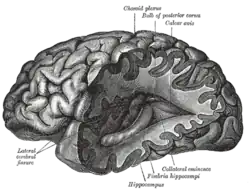

Neurology (from Greek: νεῦρον (neûron), "string, nerve" and the suffix -logia, "study of") is the branch of medicine dealing with the diagnosis and treatment of all categories of conditions and disease involving the nervous system, which comprises the brain, the spinal cord and the peripheral nerves.[1] Neurological practice relies heavily on the field of neuroscience, the scientific study of the nervous system.

Physical examination

During a neurological examination, the neurologist reviews the patient's health history with special attention to the patient's neurologic complaints. The patient then takes a neurological exam. Typically, the exam tests mental status, function of the cranial nerves (including vision), strength, coordination, reflexes, sensation and gait. This information helps the neurologist determine whether the problem exists in the nervous system and the clinical localization. Localization of the pathology is the key process by which neurologists develop their differential diagnosis. Further tests may be needed to confirm a diagnosis and ultimately guide therapy and appropriate management. Useful adjunct imaging studies in neurology include CT scanning and MRI. Other tests used to assess muscle and nerve function include nerve conduction studies and electromyography.

Neurologists examine patients who are referred to them by other physicians in both the inpatient and outpatient settings. Neurologists begin their interactions with patients by taking a comprehensive medical history, and then performing a physical examination focusing on evaluating the nervous system. Components of the neurological examination include assessment of the patient's cognitive function, cranial nerves, motor strength, sensation, reflexes, coordination, and gait.

In some instances, neurologists may order additional diagnostic tests as part of the evaluation. Commonly employed tests in neurology include imaging studies such as computed axial tomography (CAT) scans, magnetic resonance imaging (MRI), and ultrasound of major blood vessels of the head and neck. Neurophysiologic studies, including electroencephalography (EEG), needle electromyography (EMG), nerve conduction studies (NCSs) and evoked potentials are also commonly ordered.[14] Neurologists frequently perform lumbar punctures to assess characteristics of a patient's cerebrospinal fluid. Advances in genetic testing have made genetic testing an important tool in the classification of inherited neuromuscular disease and diagnosis of many other neurogenetic diseases. The role of genetic influences on the development of acquired neurologic diseases is an active area of research.